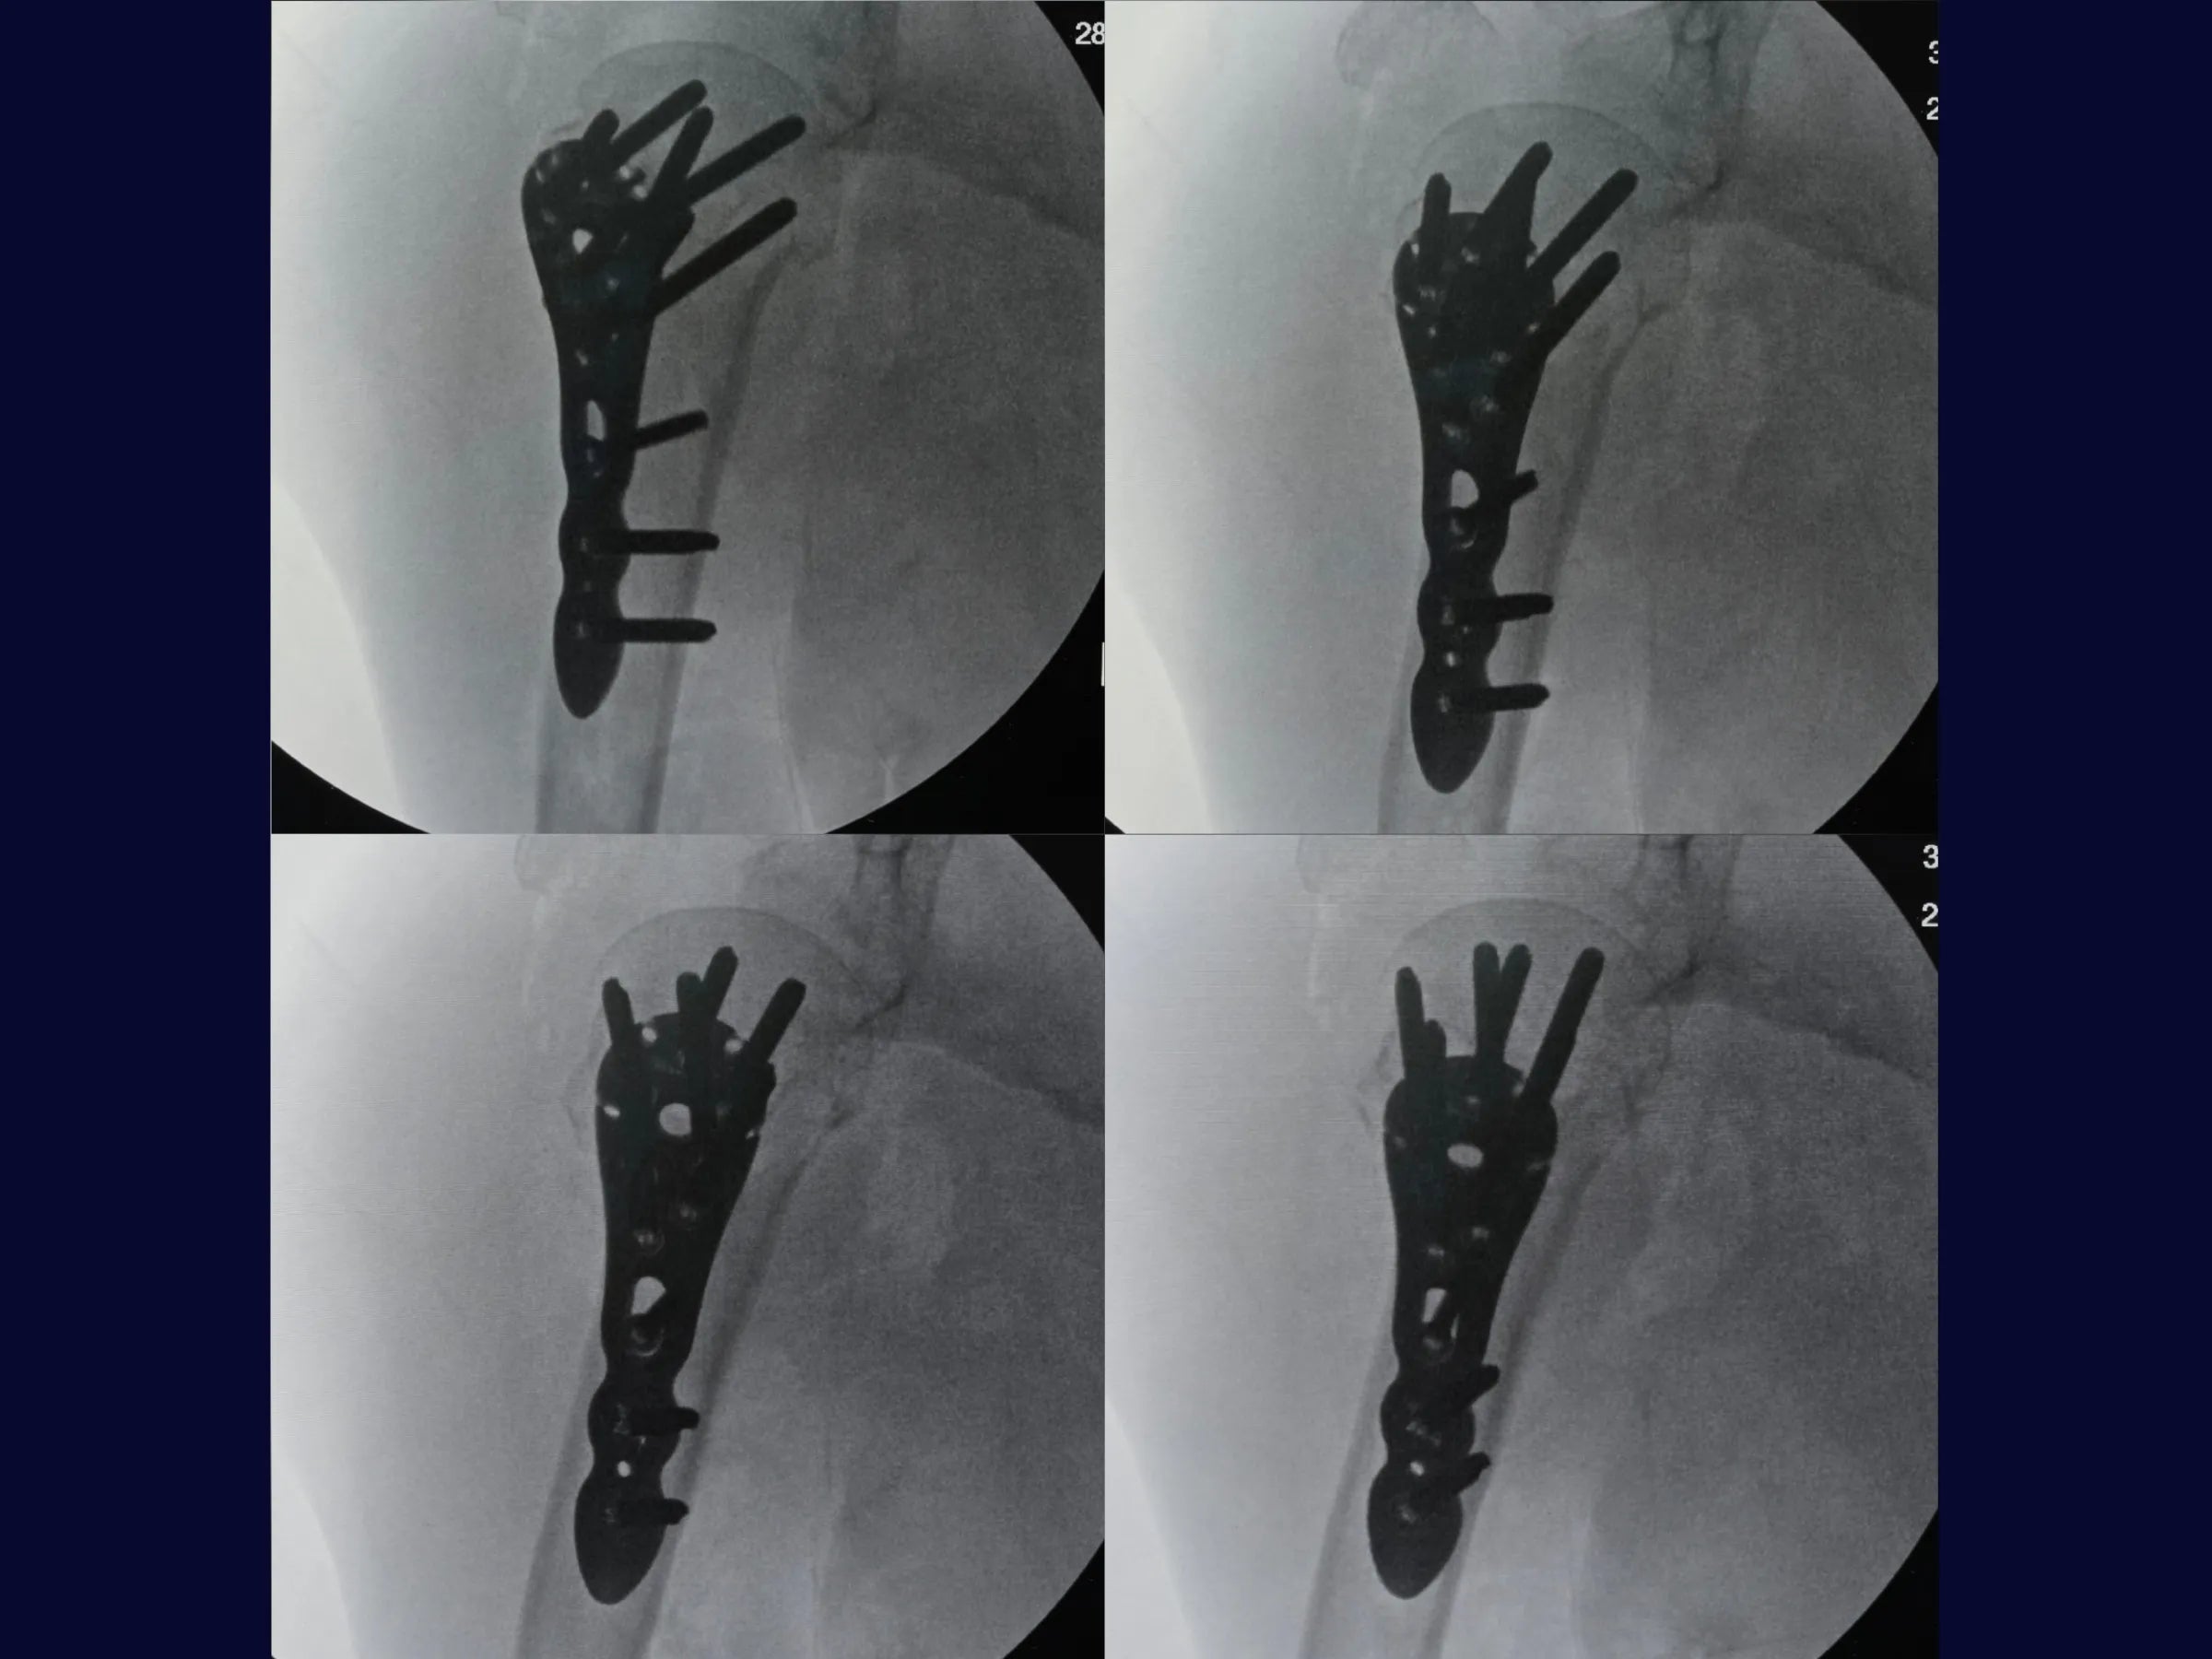

- Controle Radiográfico e Ajustes Finais: Correção de cisalhamento e simetria com reposicionamento de parafusos.